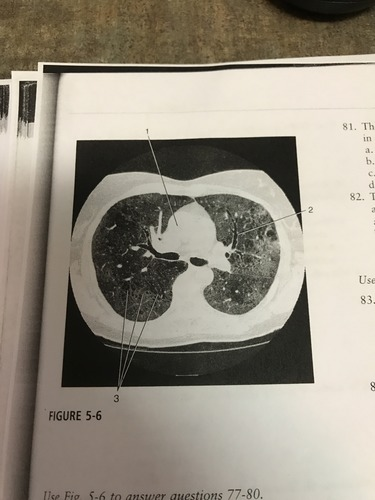

The pathological process indicated by number 3 on the figure most likely corresponds to:

A) atelectasis

B) lymphadenopathy

C) pleural effusion

D) ground- glass opacity

Number 1 on the figure corresponds to what?

A) right atrium

B) pulmonary trunk

C) ascending aorta

D) right ventricle

This HRCT image of the chest was most likely acquired with a section width of:

A) 1mm

B) 5mm

C) 7mm

D) 10mm

Number 2 on the figure corresponds to which of the following?

A) Left mainstem bronchus

B) anterior segment of the left upper lobe bronchus

C) posterior segment of left upper lob bronchus

D) anterior segment of left lower lobe bronchus